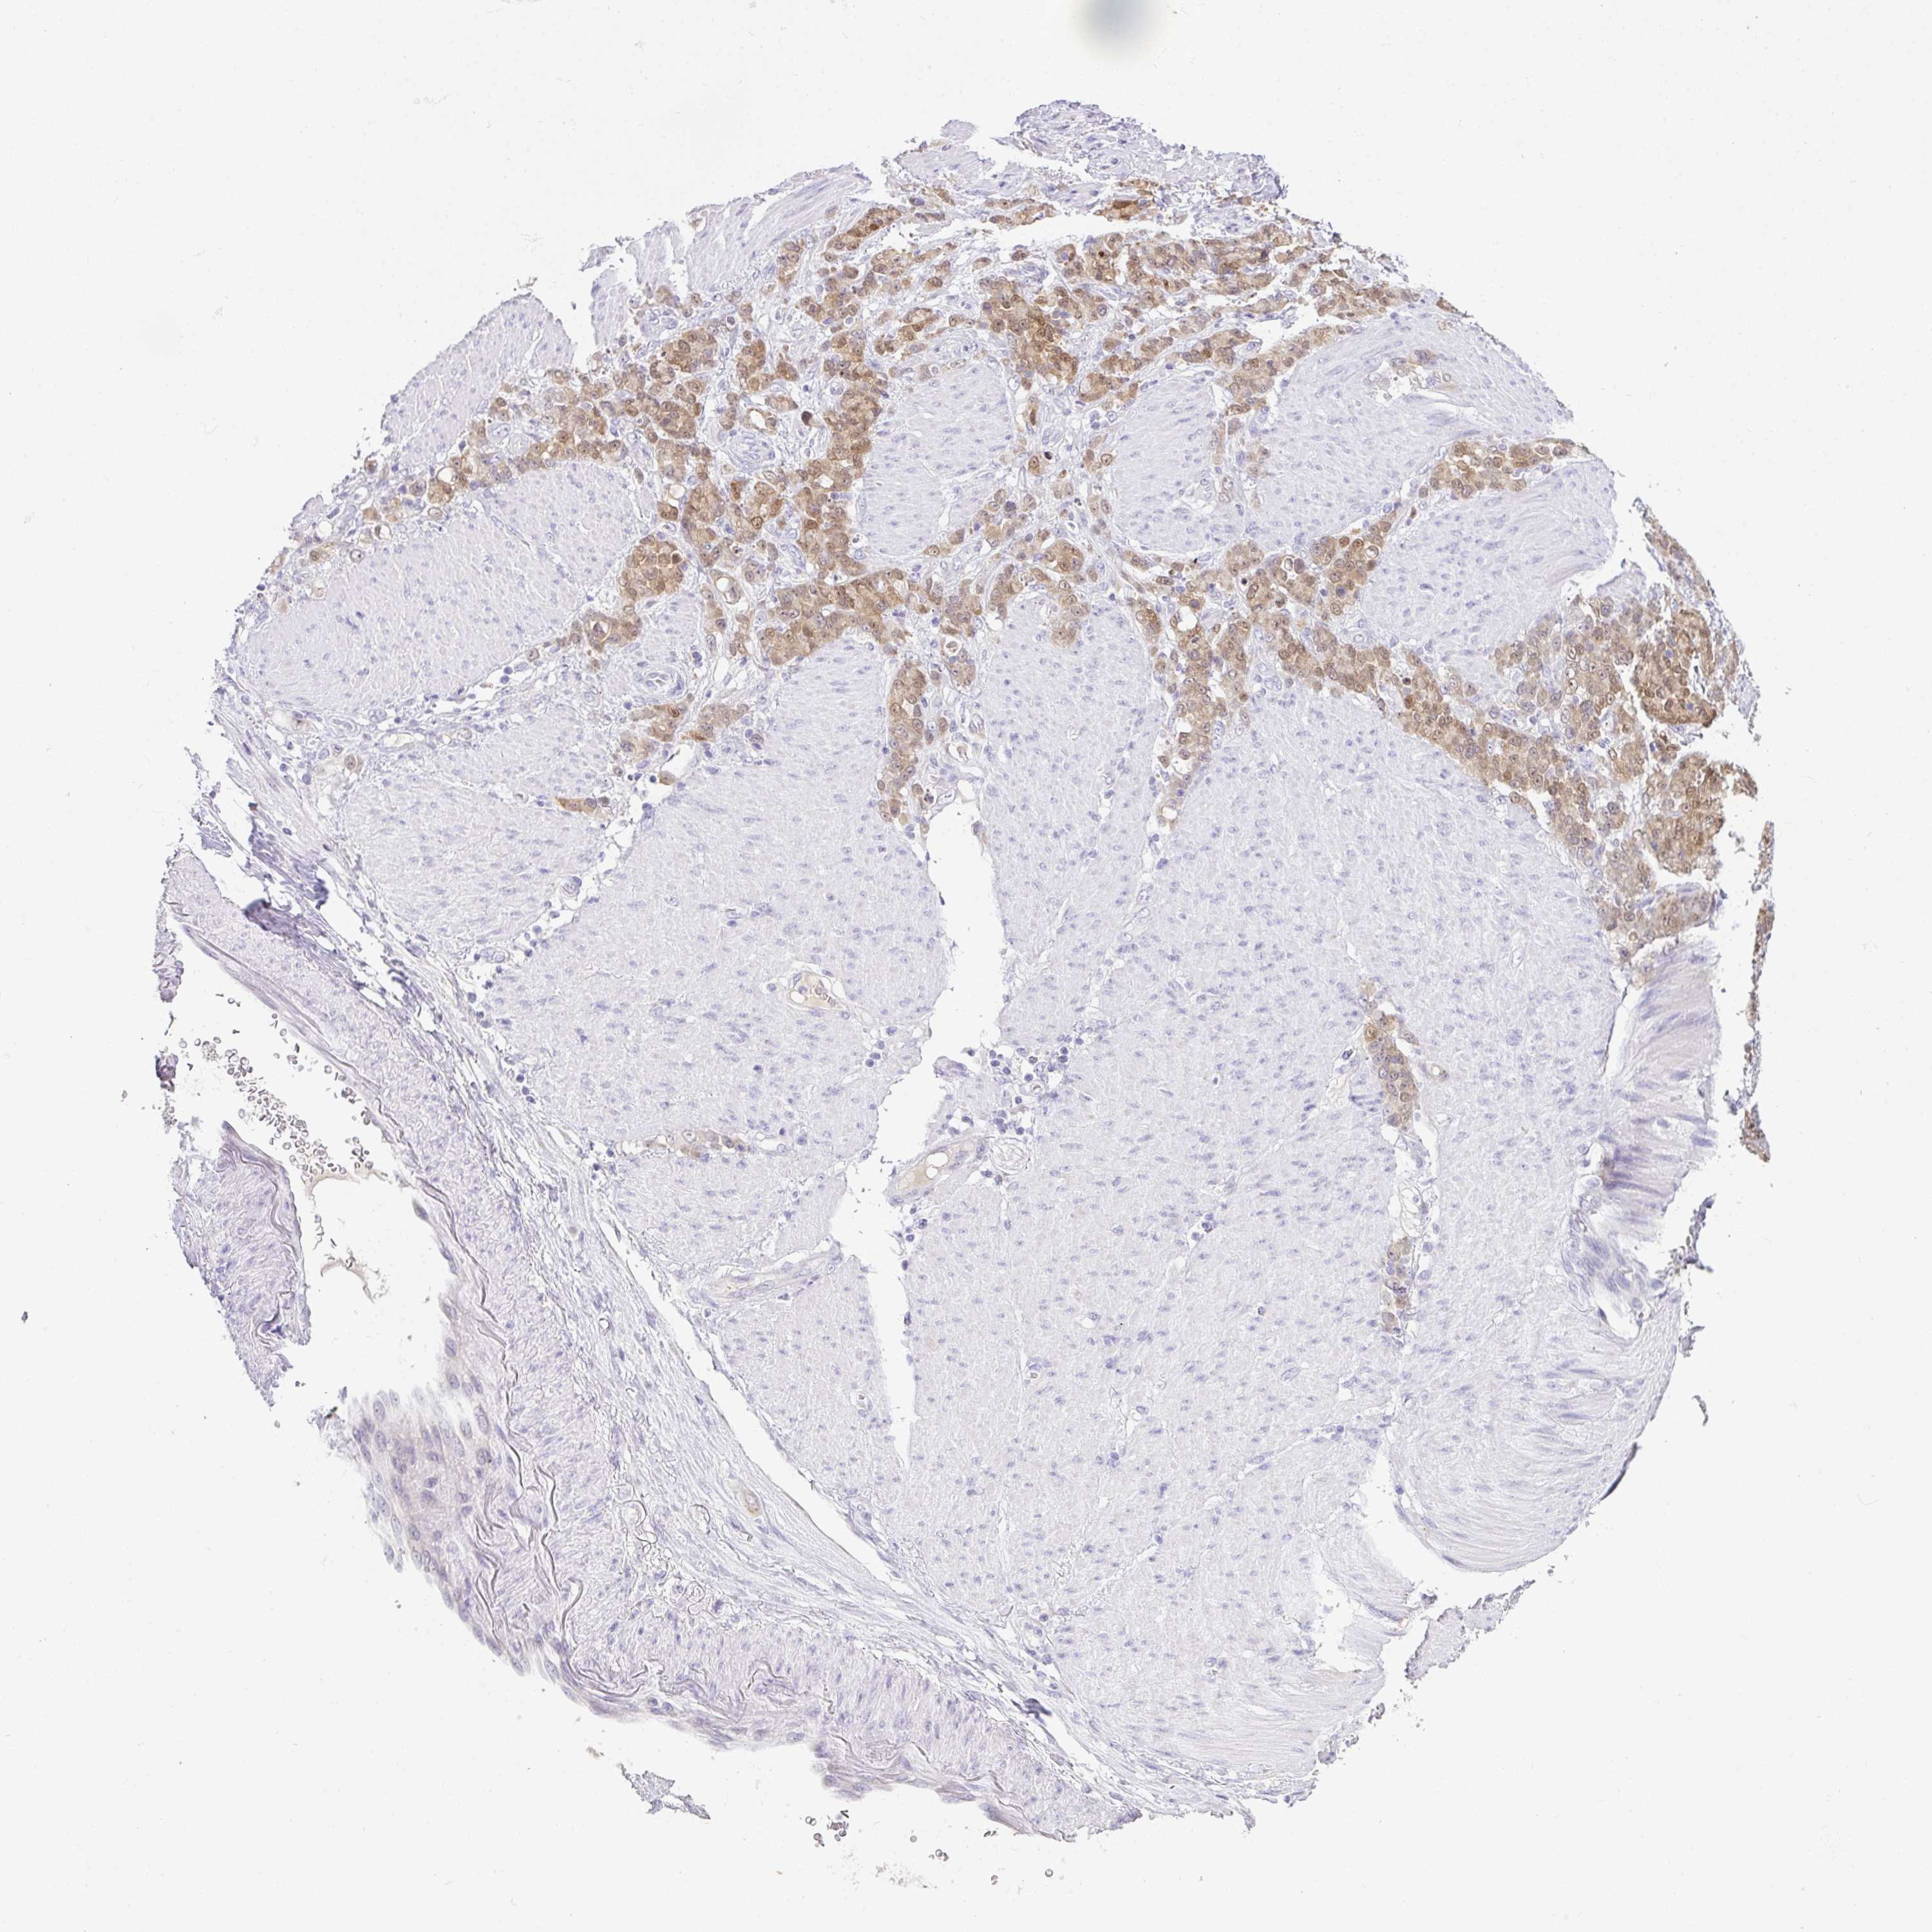

STOMACH CANCER - Protein expressioni

A mouse-over function shows sample information and annotation data. Click on an image to view it in a full screen mode. Samples can be filtered based on level of antibody staining by selecting one or several of the following categories: high, medium, low and not detected. The assay and annotation is described here.

Note that samples used for immunohistochemistry by the Human Protein Atlas do not correspond to samples in the TCGA dataset.

Antibody stainingi

Antibody staining in the annotated cell types in the current human tissue is reported as not detected, low, medium, or high, based on conventional immunohistochemistry profiling in selected tissues. This score is based on the combination of the staining intensity and fraction of stained cells.

Each image is clickable and will lead to virtual microscopy that enables deeper exploration of all samples and also displays staining intensity scores, fraction scores and subcellular localization as well as patient and tissue information for each sample.

Antibody HPA053730

Antibody HPA058604

Staining

High

Medium

Low

Not detected

Intensity

Strong

Moderate

Weak

Negative

Quantity

>75%

75%-25%

<25%

None

Location

Nuclear

Cytoplasmic/membranous

Cytoplasmic/membranous,nuclear

Adenocarcinoma, NOS